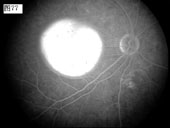

[组图]优秀眼底图片奖网上评选活动启动         ★★★

优秀眼底图片奖网上评选活动启动

优秀眼底图片奖应征作品展示